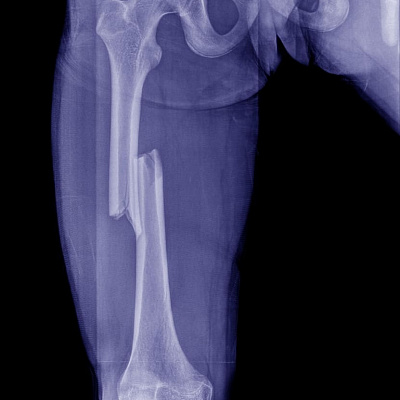

Перелом со смещением

Перелом со смещением — это нарушение структурной, анатомической целостности костной ткани конечностей, грудной клетки и прочих структур опорно-двигательного аппарата с изменением нормального положения отломков. Патологическое состояние классифицируется как сложный перелом. Симптомы расстройства выраженные. Наблюдаются сильные болевые ощущения. Присутствует заметная деформация. Без достаточного лечения такие переломы не срастаются. Развиваются осложнения, инвалидизирующие последствия патологического состояния.

Диагностика перелома со смещением отломков проводится под контролем травматолога. Задача решается инструментальными методами. На первичном приеме врач осматривает конечность, узнает жалобы и оценивает обстоятельства получения травмы. Затем проводится рентгенография. Рентген при переломе со смещением позволяет констатировать факт получения травмы и определить степень, направление смещения костного фрагмента (фрагментов).